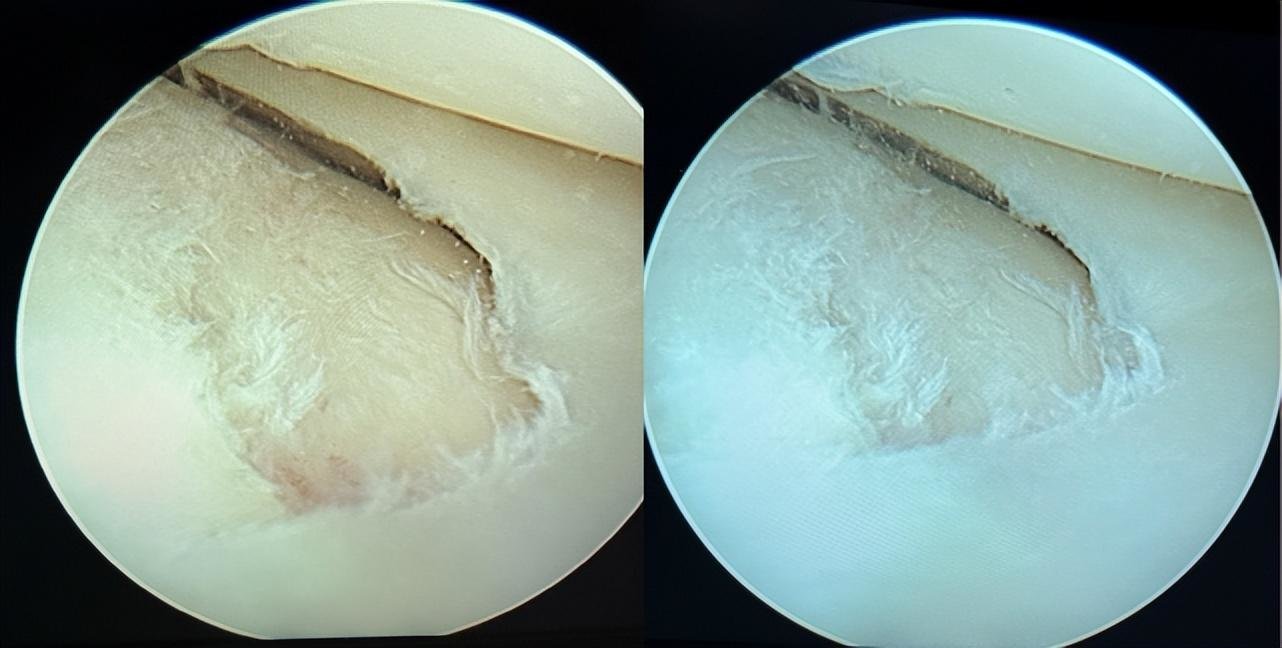

胫骨平台骨折,schatzker 3型,关节镜辅助下复位内固定手术!

如何满意复位塌陷骨块胫骨平台骨折

请教手术怎么做,右胫骨平台外侧,后侧塌陷